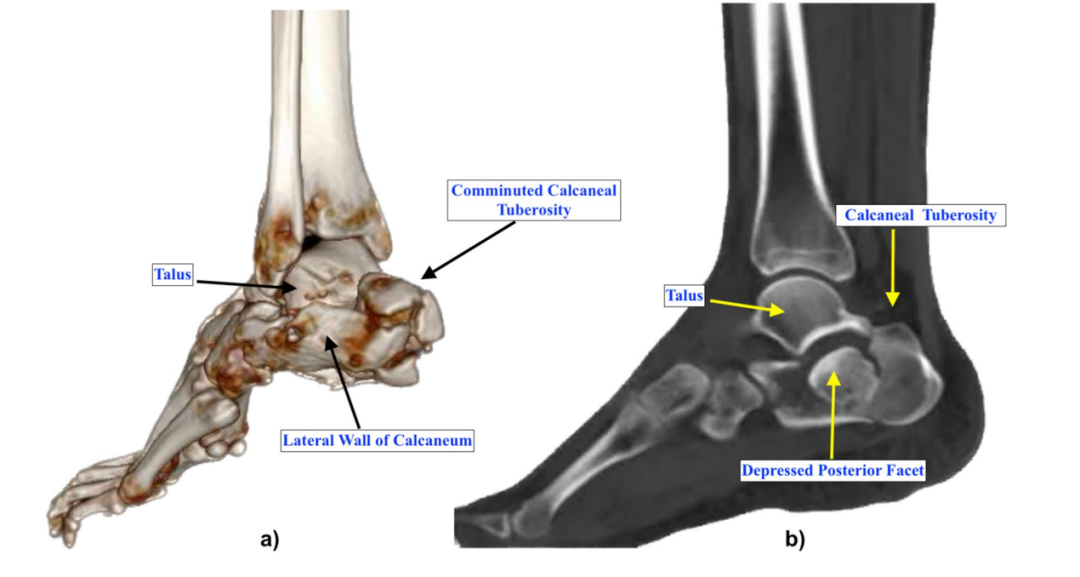

▲图示跟骨结节粉碎性骨折(a)及后关节面不连续(b)的示例,此类病例采用传统摇杆技术进行关节面修复往往效果不佳。

该技术适用于具有完整软骨下骨的主要关节面骨折块的塌陷型跟骨骨折,因为该技术需借助软骨下骨的支撑来抬起塌陷的关节面骨折块。根据Sanders分型,该技术可用于2A、2B、2C型骨折;对于部分3AC型(后关节面外侧骨折线所涉及的后关节面部分较小)和3BC型(后关节面内侧骨折线所涉及的后关节面部分较小)骨折,若其他技术难以重建,也可选用该技术。此外,对于关节面骨折块向结节延伸部分较脆弱、插入斯氏针或史氏针可能导致其断裂的病例,该技术同样适用。但对于大多数Sanders 3型和4型骨折等存在多个主要后关节面骨折块的情况,不推荐使用该技术;若跟骨外侧壁严重粉碎,该技术也难以对塌陷骨折块形成足够的撬拨力,同样不适用。